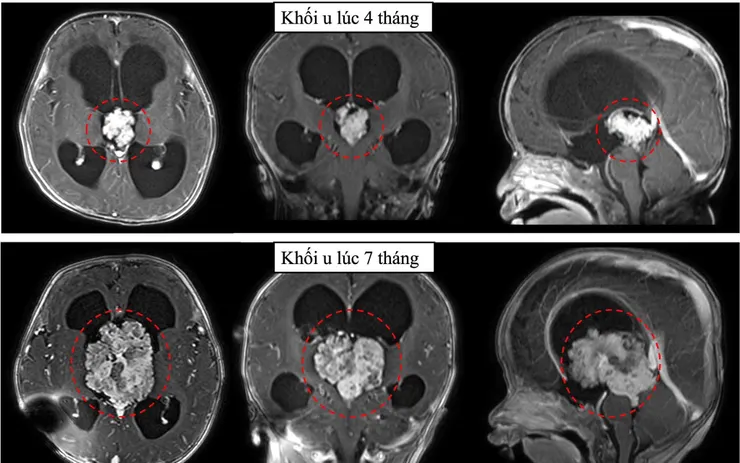

Do nguy cơ phẫu thuật cao ở trẻ nhỏ, ekip đã đặt dẫn lưu não thất - ổ bụng tạm thời để giảm áp lực nội sọ. Tuy nhiên, sau 3 tháng, khối u phát triển nhanh, tăng kích thước hơn 3 lần, buộc phải can thiệp phẫu thuật.

Ca mổ được tiến hành với sự phối hợp của nhiều chuyên khoa. Sau 6 giờ, khối u kích thước khoảng 6 cm đã được bóc tách thành công. Đây là ca mổ đặc biệt khó do vị trí u nằm sâu, gần nhiều cấu trúc thần kinh và mạch máu quan trọng, đồng thời nguy cơ mất máu cao ở bệnh nhi nhỏ tuổi.